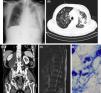

A 81-year-old male presenting with dyspnea, respiratory failure, chest radiography and thoracic CT abnormalities (Fig. 1A and B) was diagnosed with pulmonary TB after mycobacteriological sputum examination. Therapy with Isoniazid, Rifampin, Pyrazinamide and Ethambutol was initiated. During hospitalization, right lower limb (RLL) edema developed, leading to the hypothesis of lymphatic compression or deep vein thrombosis. Abdominal, pelvic and RLL CT were performed, with identification of right psoas abscess extending to L5 (Fig. 1C). Dorsolumbar spine MRI showed osteolytic and blastic lesions of D12 with cortical disruption, paravertebral soft tissue mass and enlargement of psoas muscle (Fig. 1D). The abscess was drained; sample smear showed acid-fast bacilli (Fig. 1E) and culture examination identified Mycobacterium tuberculosis, confirming bone involvement by TB with extension to the psoas muscle. Therapy was maintained for 12 months. Follow-up spine X-ray showed good evolution. Skeletal TB accounts for 1–3% of all TB cases and 10–35% of extrapulmonary TB, spinal involvement being the most common.1,2 However, only up to 5% of spinal TB patients develop psoas abscesses during disease course.1 Although identification of Mycobacterium tuberculosis in spinal lesions remains essential for definitive diagnosis, previous documentation from an extraspinal site is sufficient to establish the diagnosis in the proper clinical setting. Orthoses are usually necessary for prevention of further spinal damage. Surgery is required in selected cases: large abscess, severe deformities, neurological deficit or poor response to medical treatment.1 Being a rare form of extrapulmonary TB with nonspecific presentation, high clinical suspicion is needed in order to reduce diagnostic delay and prevent increased morbidity.

(A) Chest X-ray (posteroanterior [PA]): Right reticulomicronodular pattern and left lung cephalocaudal infiltrates; (B) Chest CT (axial plan [AP]): Bilateral micronodular opacities, right ground-glass opacities and extensive left consolidation areas; (C) Abdomen CT (coronal plan [CP]): Right retroperitoneal and retrocrural collection measuring 9×5.5cm, with inferior extension to L5 and bone destruction of the right lateral slope of D12; (D) Dorsolumbar spine MRI (sagittal plan [SP]): Signal heterogeneity suggestive of lytic and blastic lesions of D12 with cortical disruption, paravertebral soft tissue mass and enlargement of the psoas muscle; (E) Acid Fast Bacilli in the fluid drained from the psoas abscess, Ziehl-Neelsen.